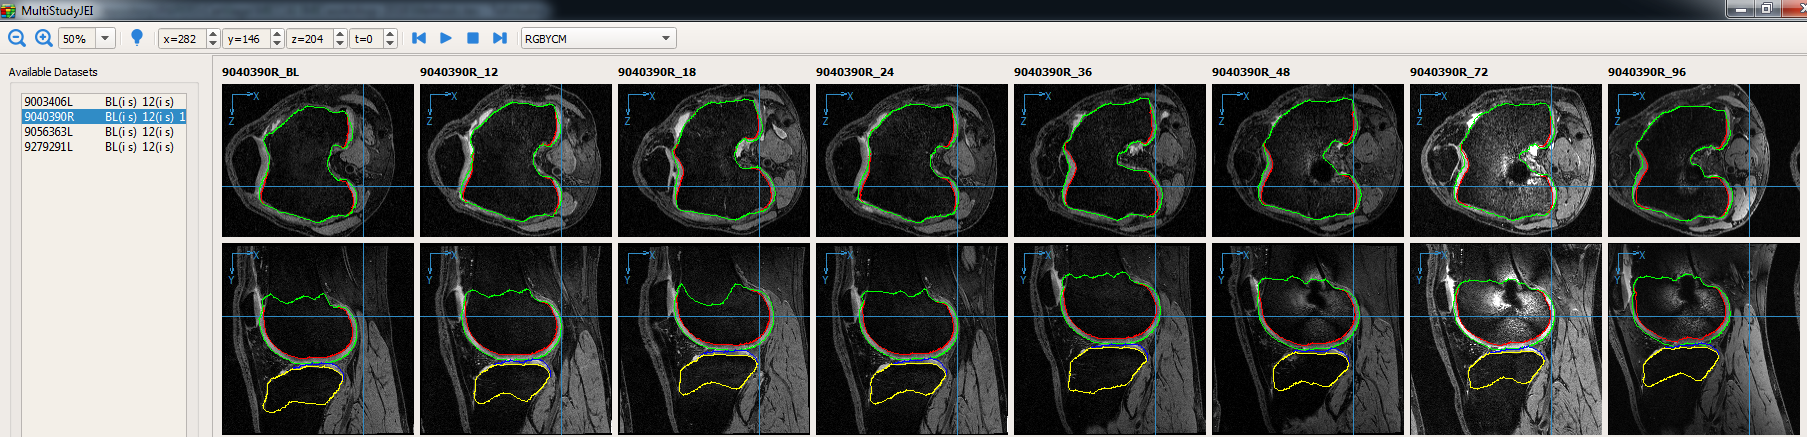

The longitudinal JEI GUI was extended to enable visualization of all patient time-points simultaneously. The viewer also enabled synchronized scrolling across datasets. Fig. 2a shows eight time-points of the same patient (baseline, 12, 18, 24, 36, 48, 72 and 96 month follow-ups) being simultaneously visualized. Each individual thumbnail view can be expanded (see Fig. 2b) to a detailed larger GUI (identical to 3D GUI) for interaction.

The interaction mechanism is similar to the 3D JEI where a set of nudge points on a single 2D slice modifies the graph node costs in the local 3D neighborhood columns of the given time-point. Further since the longitudinal JEI has has a single large underlying residual graph with temporal inter-time-point constraints the corresponding local 3D neighborhood column locations at the other time-points are also corrected.